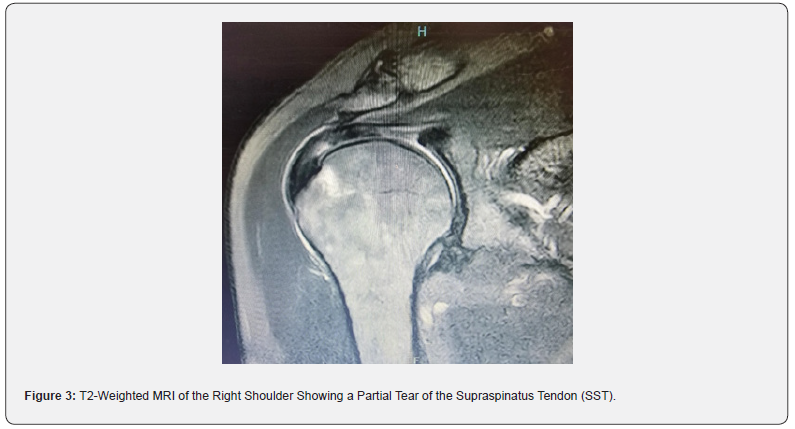

This section outlines the key performance metrics used to evaluate the accuracy of MRI in diagnosing rotator cuff injuries. True Positive (TP) refers to the number of cases where MRI correctly identified a tear, subsequently confirmed by surgery. In this sample, 91 cases were identified as true positives, demonstrating a high capability of MRI to detect tears accurately. A T2-weighted MRI scan of the right shoulder demonstrates a complete tear of the supraspinatus tendon (SST). The image highlights the disrupted tendon fibers and associated fluid signal, which are hallmark features of a full-thickness tear. T2-weighted sequences are particularly effective in visualizing soft tissue injuries due to their ability to emphasize fluid accumulation and inflammation. This finding aligns with the surgical confirmation of rotator cuff injuries, reinforcing the high sensitivity of MRI in detecting full-thickness tears and its critical role in pre-surgical planning and clinical decision-making (see Figure 2 in the Appendix). Additionally, another T2-weighted MRI scan shows a partial tear of the supraspinatus tendon (SST), emphasizing the limitations of MRI in detecting partial-thickness tears. The image reveals subtle disruptions in tendon fibers with less pronounced fluid signal compared to full-thickness tears. Such findings highlight the diagnostic challenge of differentiating between partial and complete tears in MRI (see Figure 3 in the Appendix).